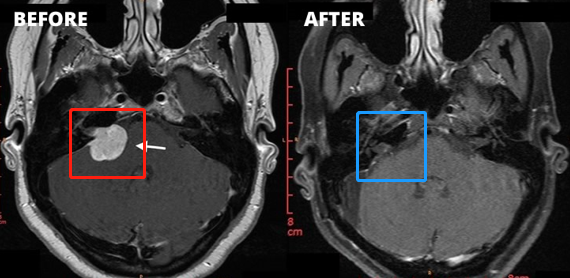

1、左侧图示(红色)患者术前核磁:右侧桥脑小脑角区见一类圆形占位性病变,边界清楚, T2WI高信号,其内信号欠均匀,增强扫描后病变呈明显强化,同侧桥脑小脑角池扩大,内听道扩大,四脑室轻微受压。

2、右侧图示(蓝色)患者术后核磁:术后肿瘤切除干净,做到了全切全切,核磁未见占位性病变。与术前对比明显可见肿瘤完整切除,较大限度减少复发可能。

3、患者术前情况:右耳耳鸣3个多月,听力下降,头昏头痛加重。面肌抽搐、舌头、牙龈和脸有麻木感觉,无法正常生活。

4、患者术后情况:术后1周出院,术后2周面神经功能House-Brackman分级1级。面神经保留,没有面瘫,听力保留。术后9个月随访,恢复很好,能够正常生活。

5、手术总结:听神经瘤切除手术规模较大的挑战是确定90%以上切除率的同时,既不损伤听神经、听力,也不损伤面神经,不会发生面瘫。以上肿瘤全切术由巴特朗菲教授操作,术后听力保留较好,且无面瘫。这样的手术效果堪称,这样的技术手法和水平即使是国际神经外科医院案例中也可以作为教科书级别的案例。